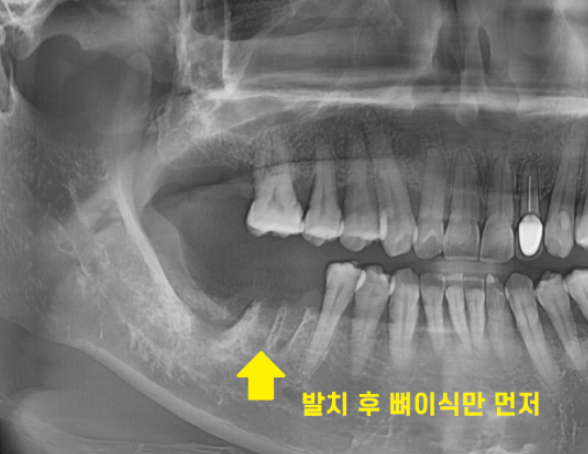

이를 뽑는 발치 후 뼈이식을 같이 진행하였습니다.

일반적으로는 임플란트와 뼈이식을 동시에 진행하지만..

뼈가 거의 없는 경우1차적으로 뼈만 이식 후

뼈가 충분히 만들어지면

추후 임플란트 수술을 진행합니다.

이렇게 되면 치료 기간이 길어진다는 단점이 있죠.